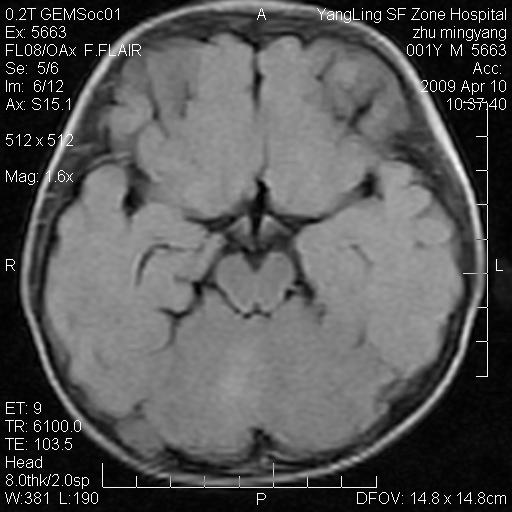

患者:1岁半,两天前外伤收住我院,ct检查小脑占位

考虑星形细胞瘤,建议增强

髓母细胞瘤或血管母细胞瘤,增强后可以鉴别;影像资料见 <。鱼博浪老师的《中枢神经系统ct与mr鉴别诊断》 小脑部肿瘤章节。

髓母细胞瘤或血管母细胞瘤!支持!

支持考虑髓母细胞瘤

考虑----髓母细胞瘤可能性大

考虑髓母细胞瘤或室管膜瘤。

支持髓母细胞瘤。

考虑髓母细胞瘤。

考虑髓母细胞瘤或星形细胞瘤

考虑髓母细胞瘤.

考虑髓母细胞瘤可能性大。

小脑肿瘤.考虑髓母细胞瘤可能.

就病灶部位及临床资料首先考虑髓母.